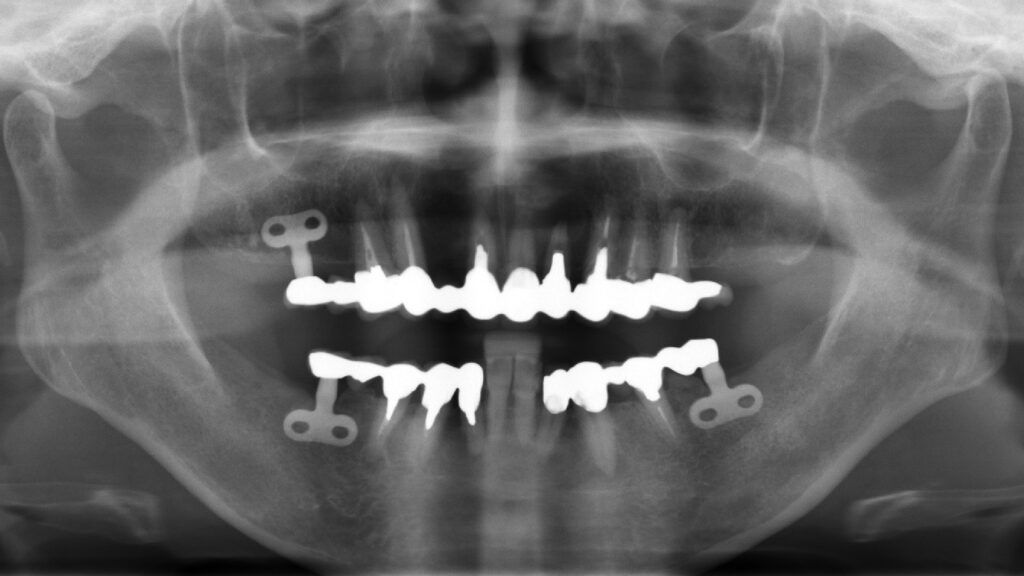

また、20年ぶりの歯科医院ということもあり歯の根やインプラント箇所に傷みが生じております。そして顎を全体的に評価すると主訴の下の前歯が歯列から飛び出し、下顎が食事や就寝時に動いたとき障害になっていることがわかりました。

| 診断名 | 不良インプラント・不正咬合・審美障害 |

| 治療方法 | インプラント治療・根管治療 |

| 抜歯部位 | FDI表記 11.13.14.22.24.25.35.44.45 |

| 治療期間 | 8ヶ月 |